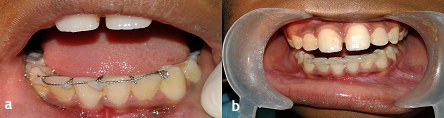

The patient was recalled after 1 month. It was observed during that time that the horizontal component lying on the incisal edges had shifted labially (Figure 7a). The shifted horizontal component was fixed in its new position with light-cured composite resin (Figure 7b).

Figure 7.a) Intraoral frontal view after 3 weeks, showing shifting of the horizontal component labially, which was previously present along the incisal edges; b) The shifted horizontal component was fixed with light-cured composite resin in its new position.